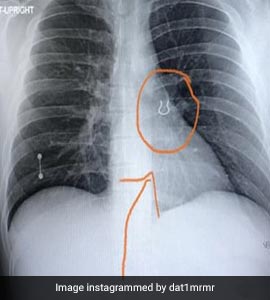

सांस के साथ फेफड़ों तक चली गई नोज़ पिन, एक्स-रे देख डॉक्टर के उड़े होश, मसां-मसां बची जान